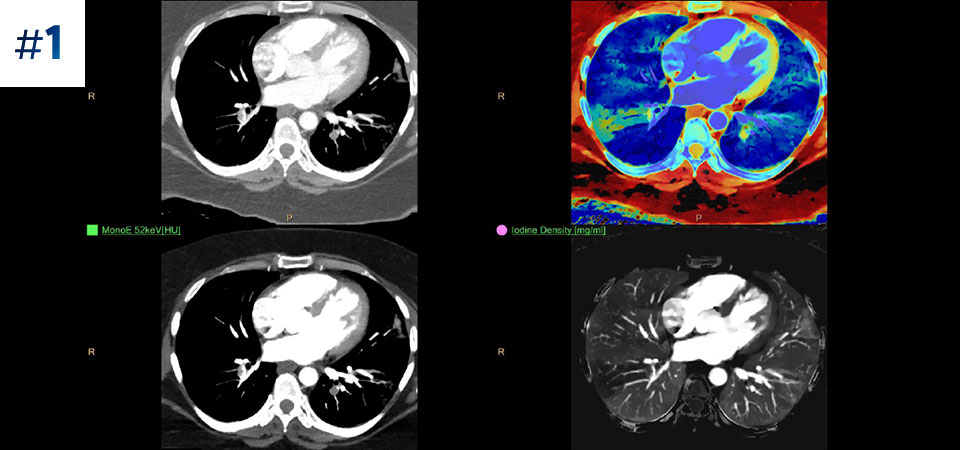

With detector-based spectral, you acquire multiple layers of data—conventional and spectral—within a single exposure and without special scan modes for improved tissue characterization and visualization.

Scan as usual A single scan for fast, low-dose conventional and spectral data for every patient, every time.

Always available 100% spectral, 100% of the time for results that are always available on-demand, even retrospectively.